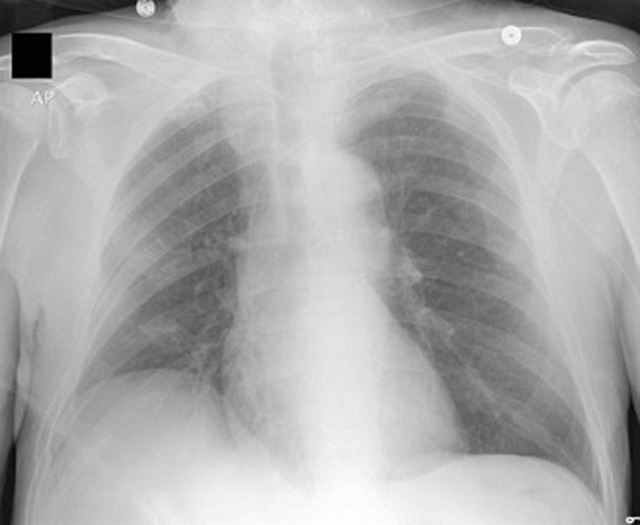

The chest film shown below is of a patient with a PICC line inserted in what appears to be the left basilic vein. See if you can follow the catheter all the way from the left arm, through the axilla, across the chest in the left subclavian and brachiocephalic veins, and finally ending just outside the right atrium in the SVC.

Image courtesy of OctavioL